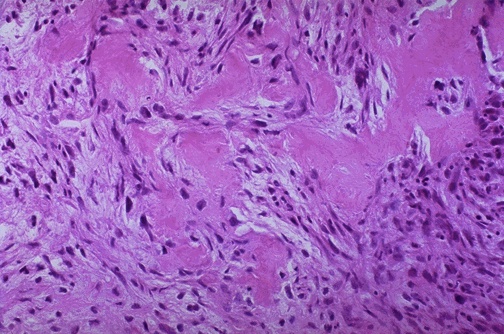

Cellular composition of osteosarcoma

Histologic feature confirming osteosarcoma

Spindle cells

Pink osteoid formation indicating differentiation